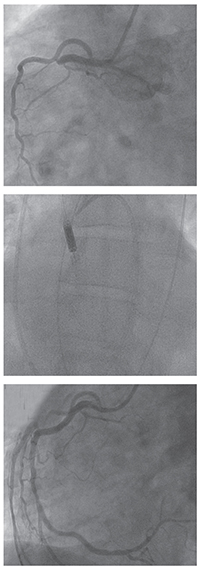

(From top to bottom): A “culprit” lesion in the proximal right coronary artery, post intervention result, and left ventricle placement of the Impella mechanical circulatory assist device to sustain cardiac output.

Patients with clear evidence of a myocardial infarction are routed immediately to the catheterization lab to undergo percutaneous coronary intervention (PCI) to open blocked coronary arteries. Smith adds, “We typically initiate PCI in appropriate patients,” in line with the 2010 AHA Guidelines for CPR and Emergency Cardiovascular Care5 which state “coma and the use of induced hypothermia are not contraindications or reasons to delay PCI…[and] PCI after [return of spontaneous circulation] in subjects with arrest of presumed cardiac etiology may be reasonable, even in the absence of a clearly defined ST-segment elevation myocardial infarction (STEMI).” Cooling and PCI may also be performed concomitantly. Large case series reports2,3 seem to indicate that early and successful PCI is associated with improved odds of survival for most patients with OHCA. Other positive prognostic signs include: time from collapse to basic life support less than five minutes; non-diabetic; age less than 59 years; initial rhythm marked by ventricular tachycardia or ventricular fibrillation; and presence of ST elevation. Additional tools such as extracorporeal membrane oxygenation (ECMO) and ventricular assist devices, can serve as what Smith refers to as “a bridge to decision,” supporting the patient while longer-term treatments are considered or prepared.